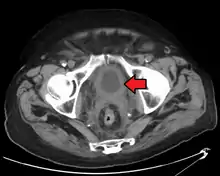

If invasive or high grade (includes carcinoma in situ) cancer is detected on TURBT, an MRI and/or CT scan of the abdomen and pelvis or urogram and CT chest should be conducted for disease staging and to look for cancer spread (metastasis).[56] Increase in alkaline phosphatase levels without evidence of liver disease should be evaluated for bone metastasis by a bone scan.[57] Although 18F-fluorodeoxyglucose (FDG)-positron emission tomography (PET)/CT has been explored as a viable method for staging, there is no consensus to support its role in routine clinical evaluations.[54]